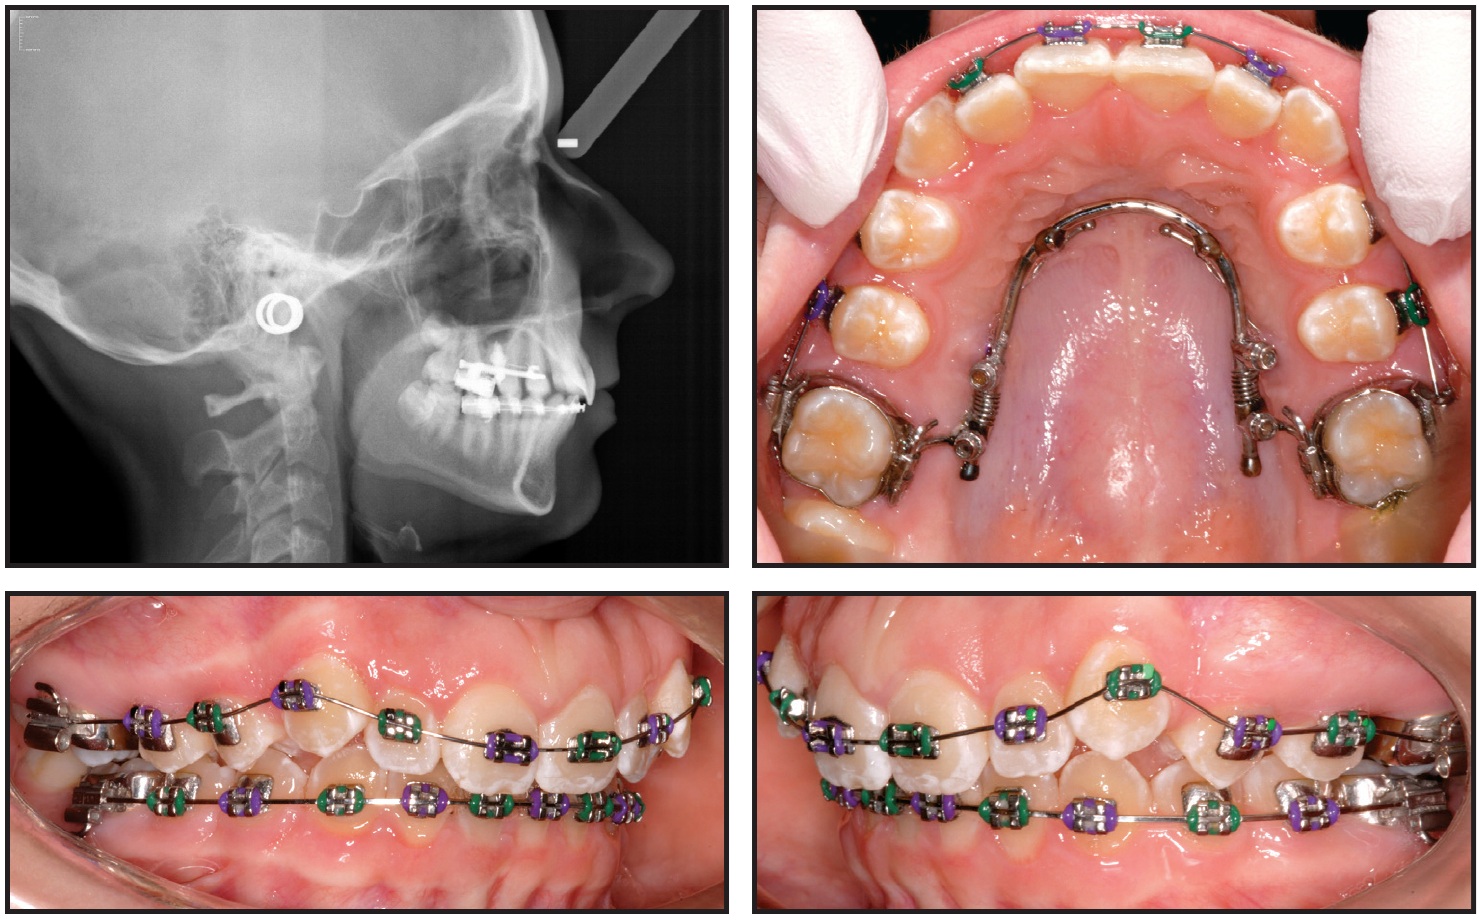

As previously described, her treatment included upper-molar distalization with a miniscrew-supported Horseshoe Jet and mandibular preadjusted fixed appliances (Fig. 4). She was instructed to use an AcceleDent device for 20 minutes daily.

Fig. 4 Preadjusted fixed appliances bonded in lower arch and miniscrew-supported Horseshoe Jet** placed for upper-molar distalization. AcceleDent prescribed for 20 minutes per day, with appointments at four-week intervals.

A Class I molar relationship was achieved in six months, with a movement rate of .8mm per month (Fig. 5).

Fig. 5 Class I molar relationship achieved after six months of treatment. AcceleDent use recorded as an average of 29 times per month.

The patient's use of vibration during that period was recorded as an average of 29 times per month. Treatment was completed in 16 months with 15 visits (Fig. 6).